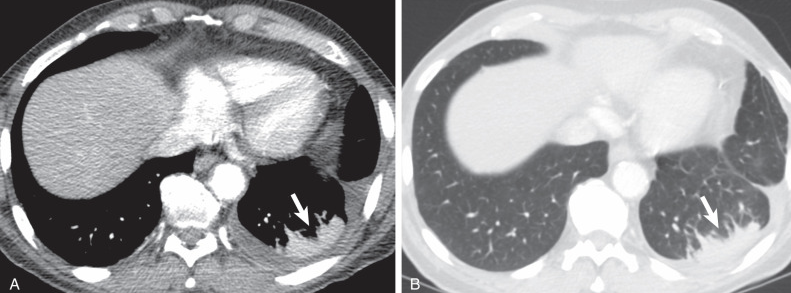

중환자실 환자에서 가장 흔한 형태의 atelectasis는

dependent atelectasis이다.

이는 중력 방향으로 폐가 눌리면서 발생한다.

대부분의 중환자실 환자는 장시간 누운 자세로 있기 때문에

폐의 뒤쪽, 즉 posterior lung 부위가 압박을 받는다.

CT에서는 폐의 후방 부위에 음영 증가가 나타나는데,

이를 폐렴으로 오해하는 경우가 많다.

하지만 자세히 보면 폐 용적 감소와 함께 나타나는 경우가 많고

체위 변화에 따라 개선되는 특징이 있다.